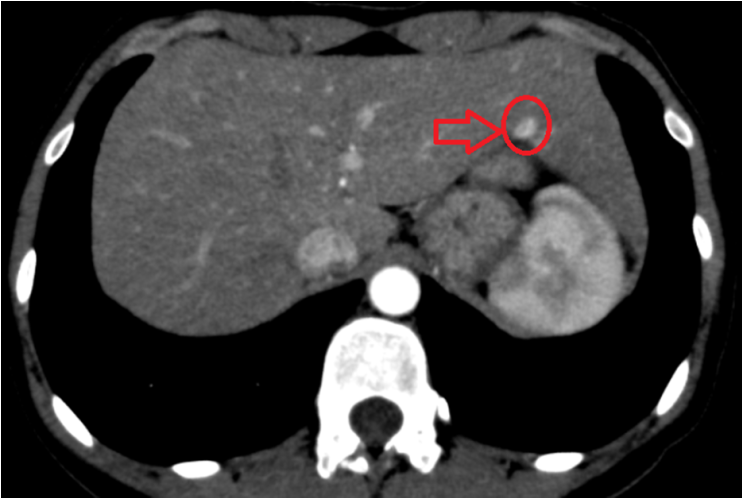

복부 초음파상에서 왼쪽 간엽에 약 1.2cm 크기의 고에코를 가지는 결절이 보이고 있습니다. 이전에 간초음파를 한 번도 한 적이 없던 환자로, 정확한 진단을 위해 추가적인 검사를 요청하여 복부CT를 진행하였습니다. 간의 왼쪽엽에 약 1.2cm 크기의 동맥기영상에서 하얗게 보이고, 지연기 영상에서 까맣게 보이는 병변을 확인할 수 있었고, 이는 일반적인 혈관종이 아니라 간선종이거나 더 나아가서 간암의 가능성까지 가지고 있는 병변입니다.

• 복부CT: 간 왼쪽엽 병변 (빨간 동그라미 표시) 복부CT: 간 왼쪽엽 병변 (빨간 동그라미 표시)